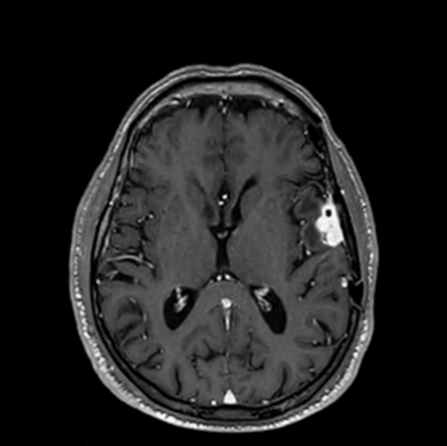

See the Difference

Compare the visual quality of our AI-enhanced images against traditional full-dose scans

AI-Enhanced

DeepGAD™ synthesized